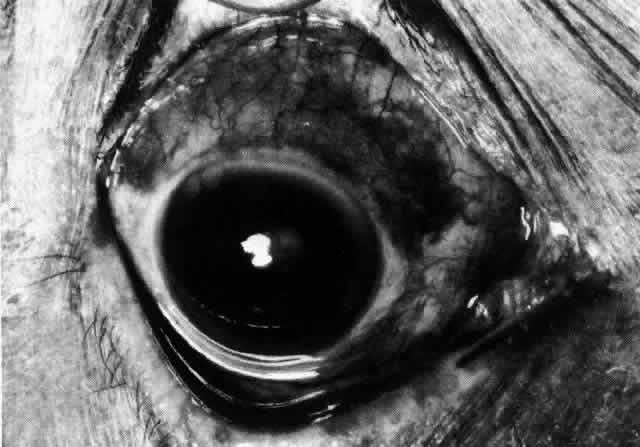

The object of slit lamp examination is to determine the depth and nature of scleral and episcleral conditions and the presence of corneal changes. The changes seen are drawn in the records. With the use of diffuse light with a neutral density filter, the vascular networks of both eyes are examined in detail to determine the layer in which the vessels show maximum congestion, the infiltration of episcleral tissues, and the edema of sclera, episclera, or subconjunctival space. Slit lamp examination is also used to ascertain the nature and depth of any corneal changes; the presence of scleral edema (for which it may be necessary to blanch the superficial tissues with epinephrine 1:1000 or phenylephrine 10%); the nature of any episcleral infiltration or mass; and the presence of cells in the anterior chamber or vitreous and posterior synechiae. The red-free (green) filter is extremely valuable in confirming the areas of maximum congestion and whether any areas are totally avascular. Because this is an important physical sign and is easily missed, examination in red-free light should be routinely performed. The green light brings the vessels into very sharp contrast with the background and enables the position of maximum inflammation to be determined with certainty. It also enables the paths and configurations of the vessels to be followed and will show lymphocytic infiltration of the episcleral tissue as yellow spots; this often indicates that the condition is more extensive than previously supposed (Fig. 8).

Fig. 8. Examination in red-free light. Blood vessels brought into sharp contrast reveal areas of lymphocytic infiltration in episcleral tissues, in this case due to herpes simplex virus.